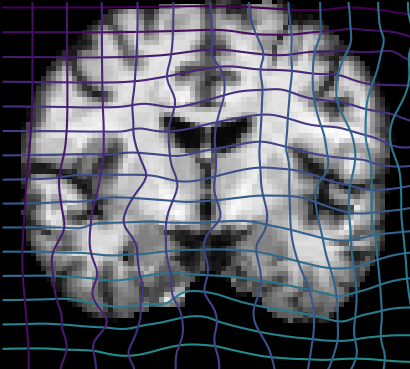

Inverse consistent rigid, affine, nonparametric, and MLP registration. We train networks on MNIST 5s using the methods in Secs. 3 and 4, demonstrating that the resulting networks are inverse-consistent. Our TwoStepConsistent (TSC) operator can be used on any combination of the networks defined in Sec. 3. For demonstrations, we join an MLP registration network to a vector field registration network, and join two affine networks to two vector field networks. Fig. 2 shows successful inverse-consistent sample registrations.

| Moving Image | Warped Image | Fixed Image | Moving Image | Warped Image | Fixed Image |